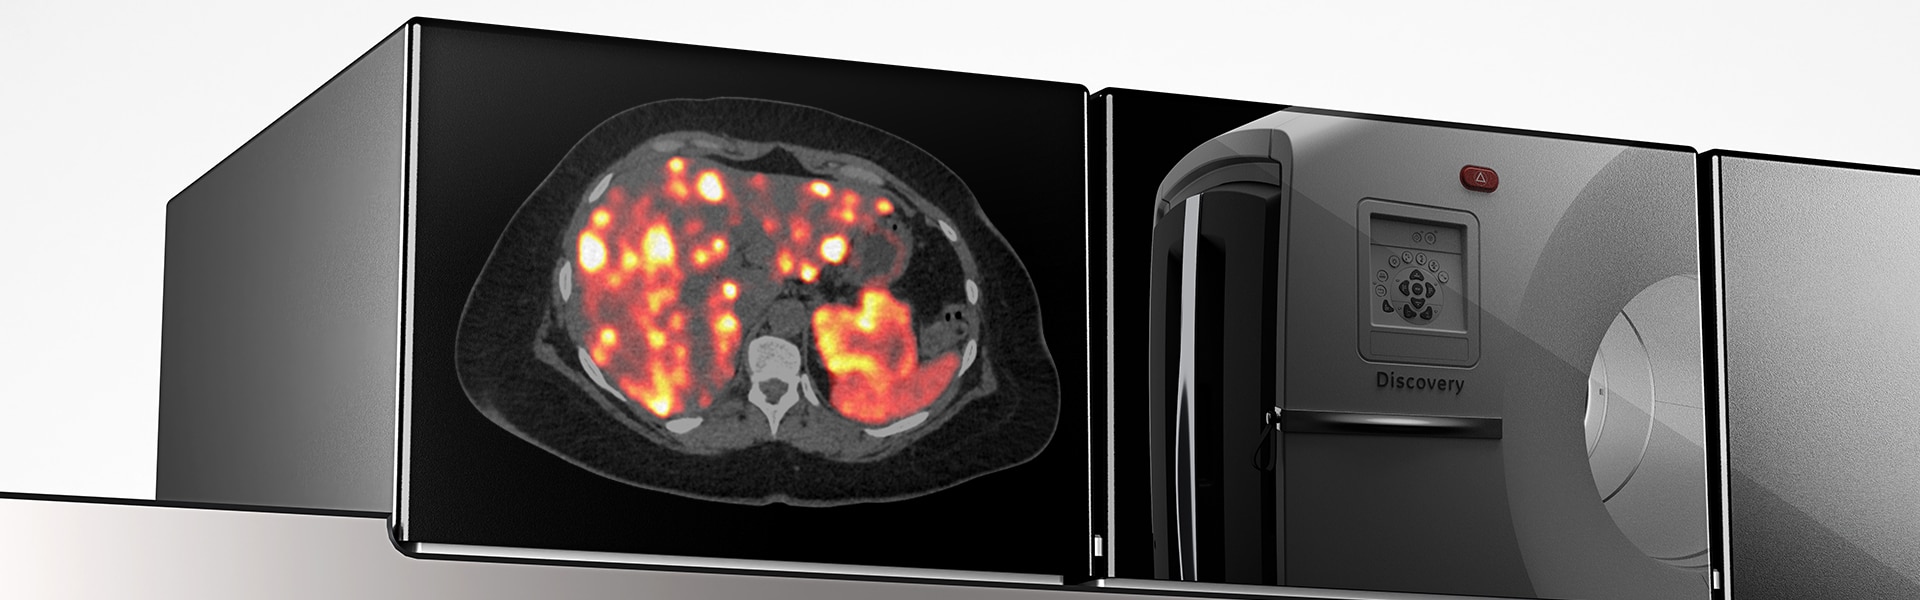

Обзор Discovery MI Gen 2

Выявление образований с помощью цифрового оборудования нового поколения

С помощью Discovery MI Gen2 вы сможете

Совершенно новый способ сканирования

- Двукратное улучшение отношения сигнал-шум в сочетании с Q.Clear

Позволяет увидеть именно то, что необходимо

Клинические изображения